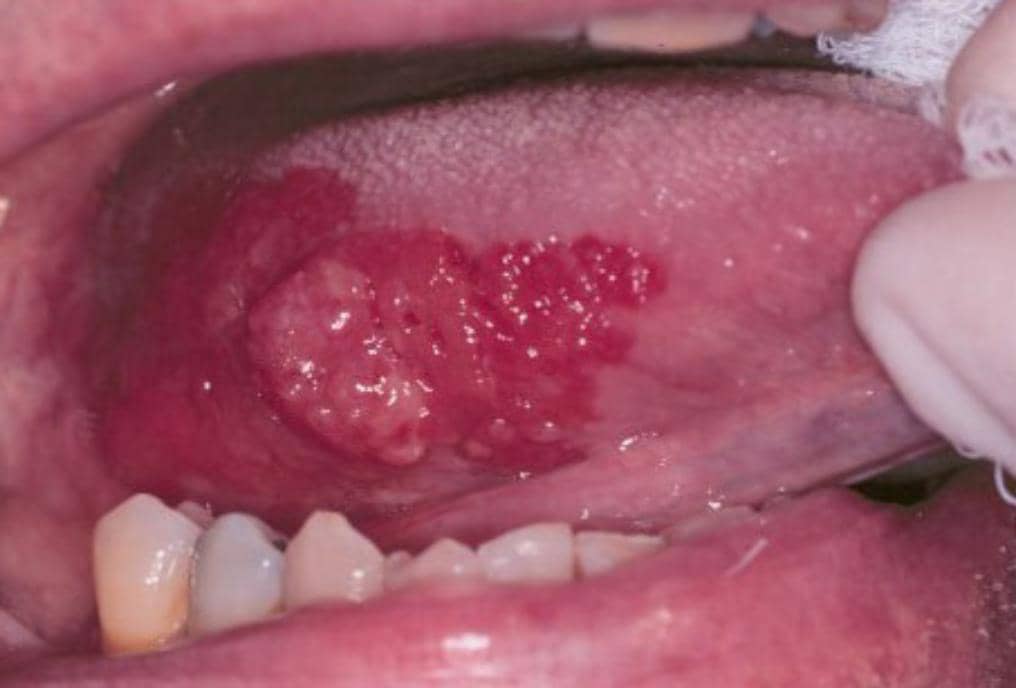

-کارسینوم سلول سنگفرشی

-علائم: زخم یا تودهای که بهسادگی خونریزی میکند و علیرغم گذشت بیش از دو هفته، بهبودی نشان نمیدهد. ممکن است با درد همراه نباشد.

-درمان: تشخیص قطعی با بیوپسی انجام میشود و درمان استاندارد شامل جراحی، شیمیدرمانی و پرتودرمانی است.

“ناحیه کف دهان، بهخصوص در افراد سیگاری و مصرفکننده الکل، مهمترین محل تشخیصی برای سرطان دهان در نظر گرفته میشود. هیچ ضایعه زیر زبان که ماهیت آن نامشخص است، نباید نادیده گرفته شود و مشاهده آن بهتنهایی کافی نیست؛ بیوپسی استاندارد طلایی تشخیص است.” (WHO)